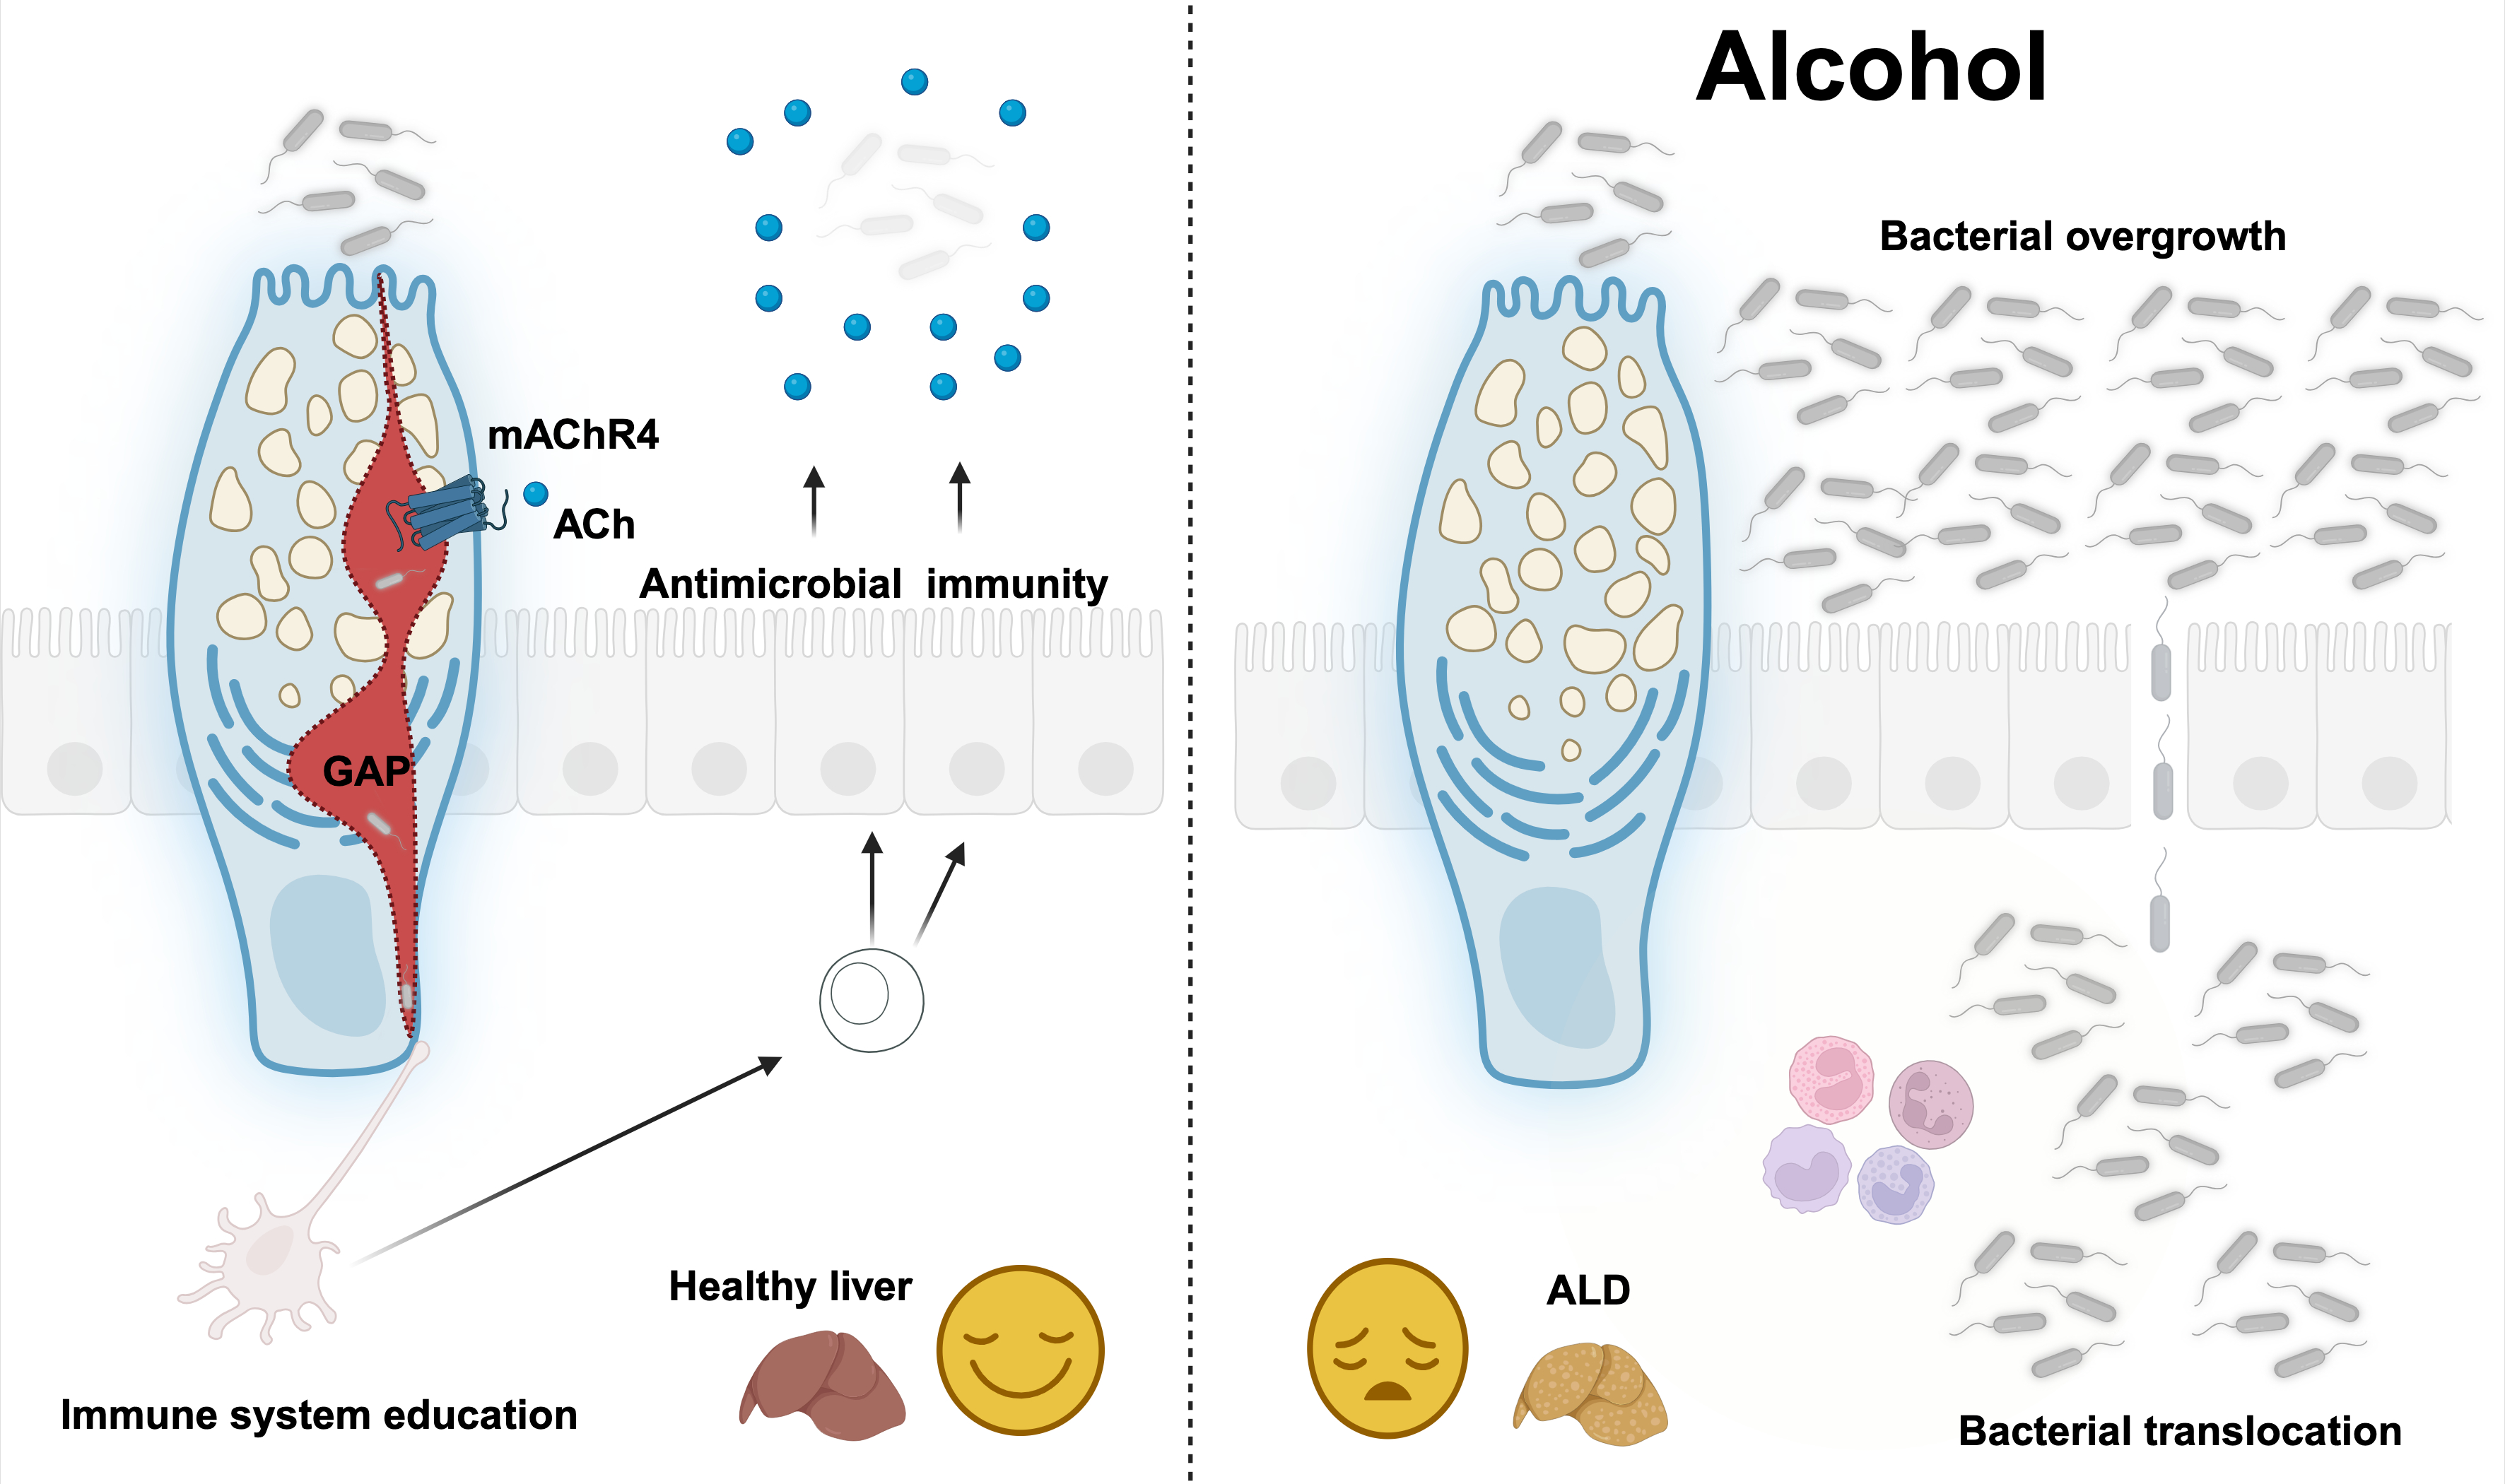

Our work: mAChR4 suppresses liver disease via GAP-induced antimicrobial immunity

Our study reveals a critical mechanism by which small intestinal GAPs, formed in response to mAChR4 activation, are essential for maintaining mucosal immune surveillance and limiting microbial translocation to the liver.

Alcohol Disrupts mAChR4-GAP-Mediated Barrier Function. Chronic alcohol exposure in both humans and mice downregulates mAChR4 expression and related pathway transcripts, leading to reduced GAP formation. mAChR4 downregulation strongly correlates with ALD progression in patients with AUD. Our preclinical models demonstrate that GAP closure is mediated through MAPK. This impairs barrier function by disrupting antigen sampling by LP-APCs, weakening antimicrobial immunity (REG3), and facilitating pathogenic bacterial translocation, a key driver of ALD progression.

GAP-Induced Immune Cascade Restores Protection. We define a novel and critical molecular mechanism involving GAP generation, which samples luminal antigens and initiates a protective, APC-mediated immune response. APCs secrete IL-23, promoting IL-22 production by ILC3s. IL-22 then acts on IECs and Paneth cells to induce antimicrobial Reg3 lectins. In summary, the GAPs → LP-APCs → IL-23 → ILC3s → IL-22 → Reg3 axis limits mucosa-associated bacteria, prevents bacterial translocation to the liver, and protects against ethanol-induced liver injury.

GAPs deliver luminal antigens to lamina propria antigen-presenting cells, educating the intestinal immune system and stimulating REG3B/G antimicrobial peptides. Figure created with a license from BioRender. -

- First Demonstration of the Protective Role of GAPs in ALD. Our goblet cell-specific manipulation of mAChR4 is the first to establish a direct immunoprotective role for GAPs in intestinal homeostasis and liver disease. These findings redefine goblet cells as key immune sentinels in the gut-liver axis and position GAP formation as a therapeutic checkpoint for ALD.

Selective AChR4 Positive Allosteric Modulation (AChR4 PAM), a promising therapy for ALD. Restoring GAP formation with an mAChR4 PAM prevents microbial translocation and ethanol-induced steatohepatitis in both WT and IEC-specific gp130-deficient mice, where disease is worsened.

Enhancement of GAP formation through IL6ST/gp130 activation, mAChR4 positive allosteric modulation (PAM), or chemogenetic GC-specific mAChR4 activation promotes expansion and function of antigen-presenting cells (APCs), strengthens gut barrier function, and prevents ethanol-increased mucosal bacteria and translocation through the GAP-APCs-ILC3-IL-22-REG3B/G axis, and Treg-mediated responses. Figure created with a license from BioRender. Figure from Llorente et al., Nature, 2025 -